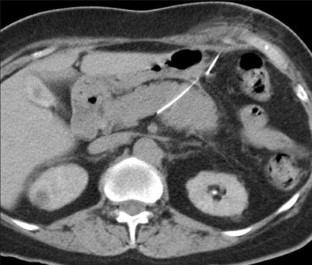

Fig. 1